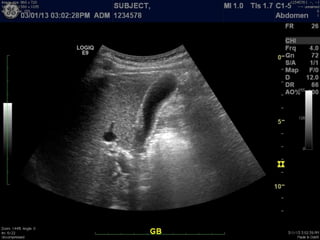

B-mode, 2D imaging

A Primer ofDiagnostic Ultrasonic Imaging Modalities B-mode, 2D imaging

3D rendering

A Primer ofDiagnostic Ultrasonic Imaging 3D rendering